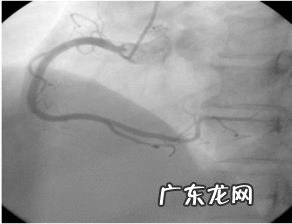

心电图提示ST段改变 , 多数时候需要结合患者自身症状 , 如果没有症状 , 大多数ST改变也不是全部提示冠心病!而如果症状明显 , 再加上心电图变化 , 那么提示心肌缺血冠心病的概率就大大升高!所以 , 发现改变后问诊结合症状尤其重要!当然 , 还有些变化可见于冠心病以外的其他疾病 , 就需要根据心脏彩超 , 心脏造影 , 心肌酶等辅助检查进行确诊了!